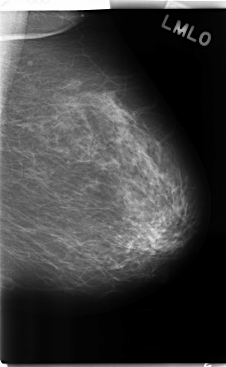

C_0242_1.LEFT_MLO

LEFT_MLO LINES 4768 PIXELS_PER_LINE 2928 BITS_PER_PIXEL 12 RESOLUTION 50 NON_OVERLAY